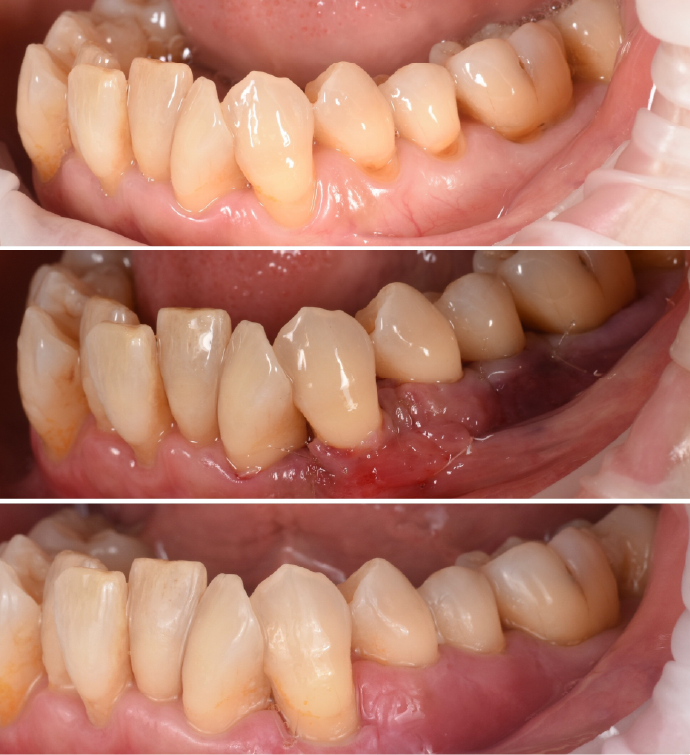

歯周病菌の炎症が歯茎の内側にも進行、歯を支える骨(歯槽骨)にも影響が出始めている段階。腫れ・出血・冷たいものがしみるなどの症状が出ることがあります。

歯槽骨の1/3〜1/2が破壊された状態。歯茎の腫れ・出血・膿・歯のぐらつき・口臭など自覚症状がかなり出ます。

歯槽骨の2/3以上が溶け、歯根が露出し、歯茎からの出血・膿・口臭・歯のグラつきがひどくなり、食事ができないほどになる事もあります。このまま放置すると自然に歯が抜け落ちる可能性があります。

| 治療内容 | 上段 根面被服術(歯茎を上げる手術) |

| 治療内容 | 下段 歯周外科(再生療法) |